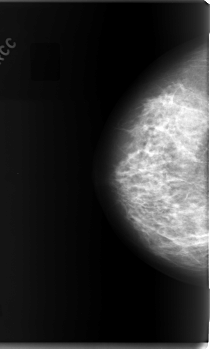

C_0070_1.RIGHT_CC

RIGHT_CC LINES 5920 PIXELS_PER_LINE 3560 BITS_PER_PIXEL 12 RESOLUTION 50 NON_OVERLAY